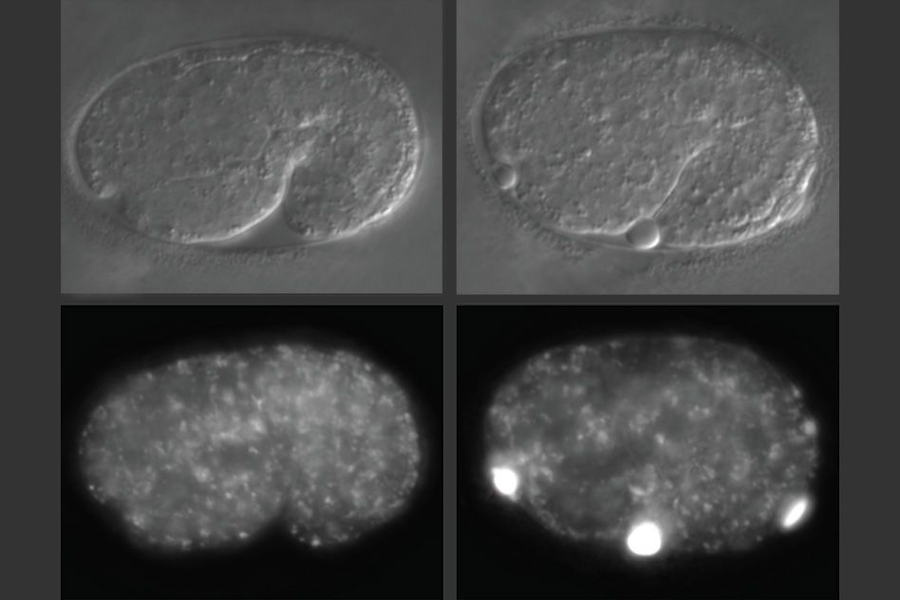

Caption: Biologists compared C. elegans embryos missing the alfa-1 gene, right, to those with the gene, left. At bottom right, abnormal blobs of yolk labeled with a fluorescent protein can be seen in the embryo lacking alfa-1.

Biologists compared C. elegans embryos missing the alfa-1 gene, right, to those with the gene, left.  At bottom right, abnormal blobs of yolk labeled with a fluorescent protein can be seen in the embryo lacking alfa-1.

In studies of worms that lack alfa-1, the researchers discovered that defects became apparent early in embryonic development. C. elegans embryos have a yolk that helps to sustain them before they hatch, and in embryos missing alfa-1, the researchers found “blobs” of yolk floating in the fluid surrounding the embryos.

This led the researchers to discover that the gene mutation was affecting the lysosomal degradation of yolk once it is absorbed into the cells. Lysosomes, which also remove cellular waste products, are cell structures which carry enzymes that can break down many kinds of molecules.